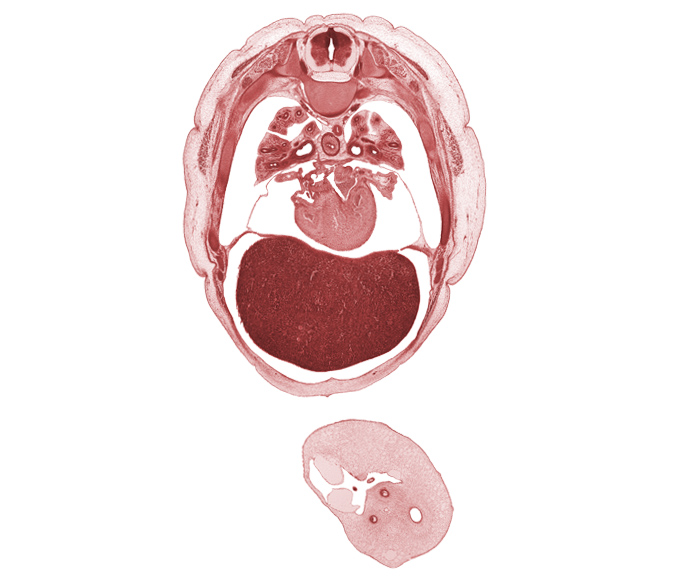

Carnegie Embryo #4090 | Location: 17-5

Keywords: T-5 intercostal nerve, T-5 spinal ganglion, T-5 spinal nerve, horizontal fissure, left ventricle, lower secondary bronchus, middle lobe of right lung, middle secondary bronchus, pericardial sac, primary interatrial septum (septum primum), rib 6, rib 7, right ventricle, secondary interatrial foramen (foramen secundum), secondary interatrial septum (septum secundum), sinus venosus, umbilical coelom, umbilical cord, umbilical vesicle stalk, upper lobe of right lung

Source: The Virtual Human Embryo.